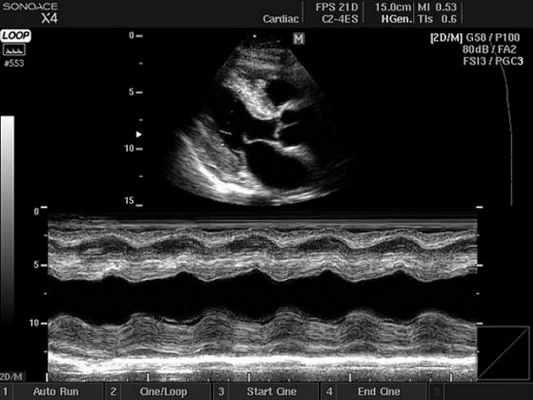

- М-режим (M-mode). Это «усеченный» вариант предыдущего, при котором используется для анализа только одномерное изображение. Основное внимание уделяется одной из линий 2D трассировки, что позволяет более детально исследовать движения створок клапанов и сердечной мышцы.

2. М-режим - графическое изображение движения стенок сердца и створок клапанов во времени. М-режим позволил впервые в реальном времени оценить размеры сердца и систолическую функцию желудочков. В настоящее время применяется как вспомогательный режим при проведении эхокардиографического исследования преимущественно для измерений. В том случае, когда в парастернальной позиции курсор М-режима располагается строго перпендикулярно изображению сердца, измерения могут быть проведены с большой точностью. Если изображение сердца и курсор расположены под углом, все размеры камер сердца будут значительно завышены и могут быть неправильно истолкованы. Эта ошибка встречается у специалистов с небольшим стажем работы. Поэтому следует проводить измерения в B- режиме в конце диастолы в том случае, если М-режим не может быть применен. В настоящее время ряд фирм предложили использовать анатомический М- режим, позволяющий изменить угол курсора.

На графике М-разверстки по вертикали откладывается расстояние, по горизонтали - время. В зависимости от положения курсора на экране, можно получить график колебания серии точек, расположенных вдоль курсора, вытянутый во времени, т.е. проследить за их колебанием в систолу и в диастолу.